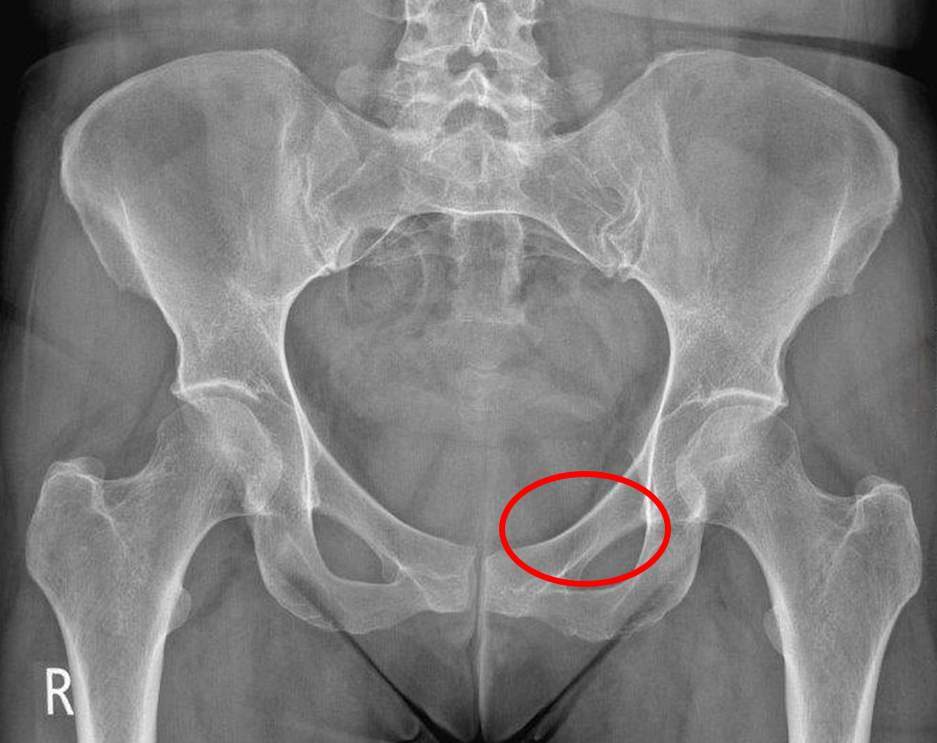

Which anatomical structure does the red circle highlight on this pelvic x-ray?

a) Iliac wing

b) Superior pubic ramus

c) Acetabulum

d) Sacrum

e) Pubic symphysis

A